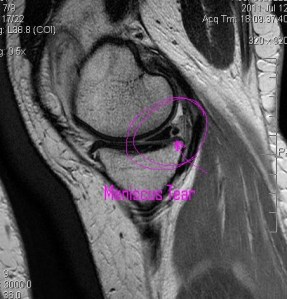

The other big thing that showed up was this tear in the meniscus. This came off the bone when the ligament tore up. You can see the arrow pointing to what sort of looks like a black circle. The black circle should be connected to the black triangle next to it. So basically there is this cushioning material that is just flapping around down there…and I’m sure that is what is causing a lot of my pain. And this is what was the cause of the blood and some of the swelling.